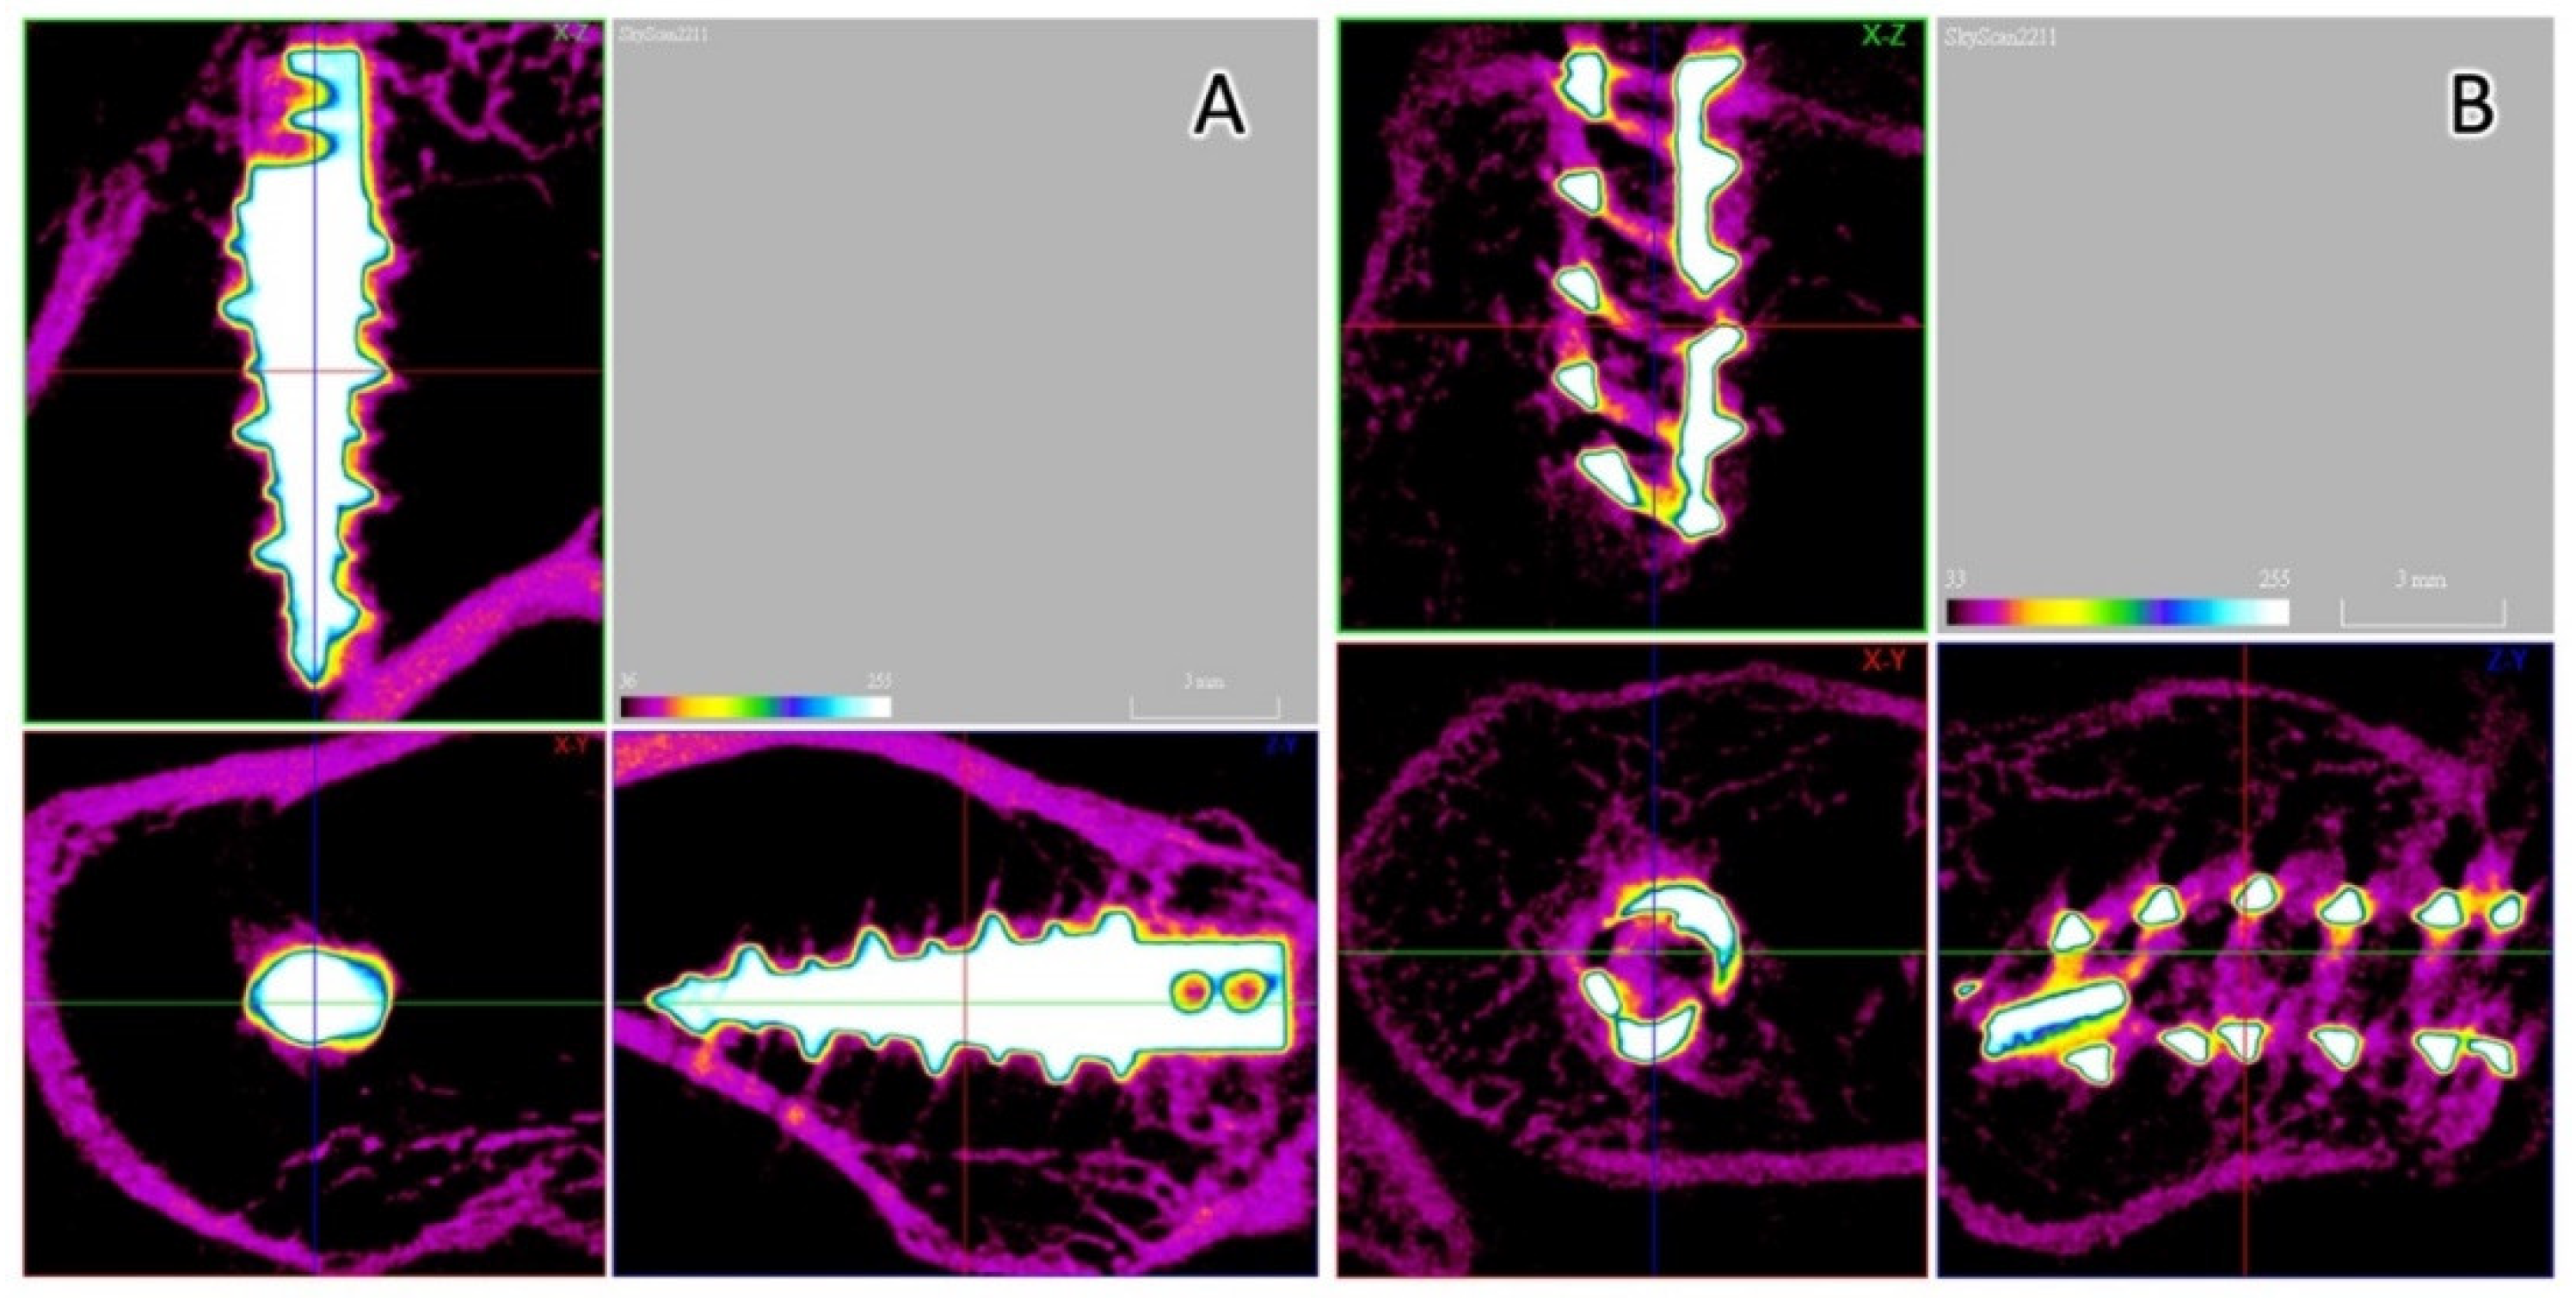

2.5. Micro-CT Analysis

3.5. Micro-CT Analysis

3.6. Histological Analyses